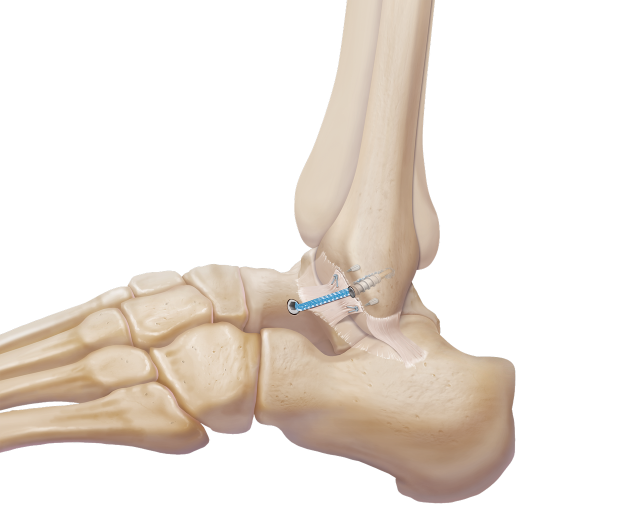

Bei frischen Verletzungen können meistens Bandanteile mit Fäden augmentiert und am Knochen wieder fixiert werden. Mitunter erfolgt die Fixierung des Bandes mittels im Knochen eingebrachter Ankersysteme, über die das Band angenäht werden kann. Um ein Ausreißen der Anker bzw Fäden verhindern zu können, werden üblicherweise „Stellschrauben", die das Wadenbein am Schienbein etwas oberhalb des Sprunggelenks fixieren, gesetzt.

Diese Schrauben müssen vor Beginn der Gehbelastung in aller Regel entfernt wieder werden. Alternativ kann ein sogenanntes Tight Rope, ein Kunstband, das über einen Bohrkanal das Schien- am Wadenbein fixiert, verwendet werden.